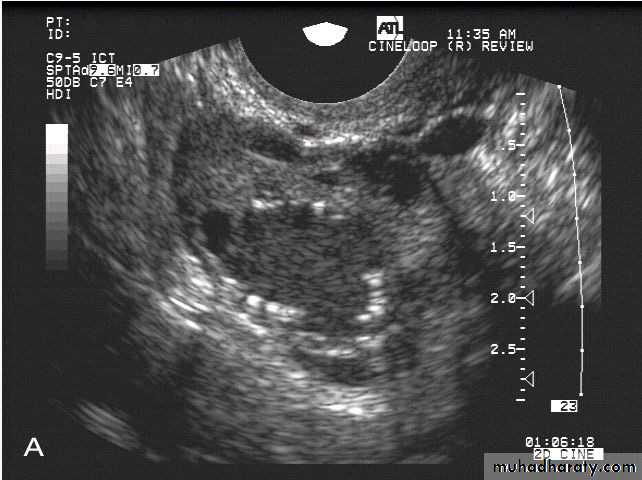

This young adult female patient was examined to evaluate the uterus and ovaries. She was under treatment for infertility and was using gonadotropins. Ultrasound images of the ovaries show grossly enlarged ovaries with large cysts (measuring 2.6 to 3 cms.) in both ovaries. These ultrasound findings are diagnostic of OHSS or ovarian hyperstimulation syndrome.

• Ovarian hyperstimulation syndrome (OHSS):

The ultrasound image again show hyperstimulated ovaries. Both ovaries are grossly enlarged and cystic.